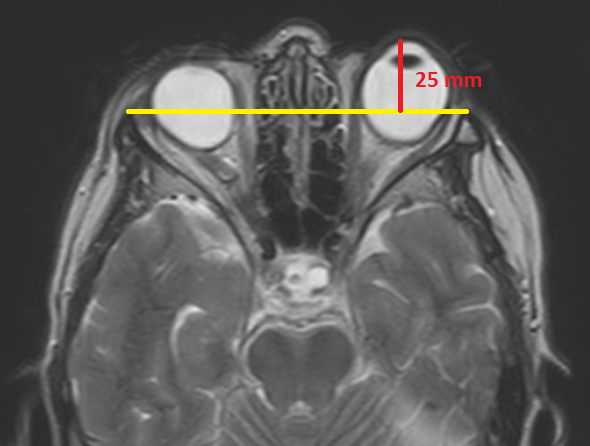

¿Cuáles son los hallazgos radiológicos en la RM del exoftalmos?